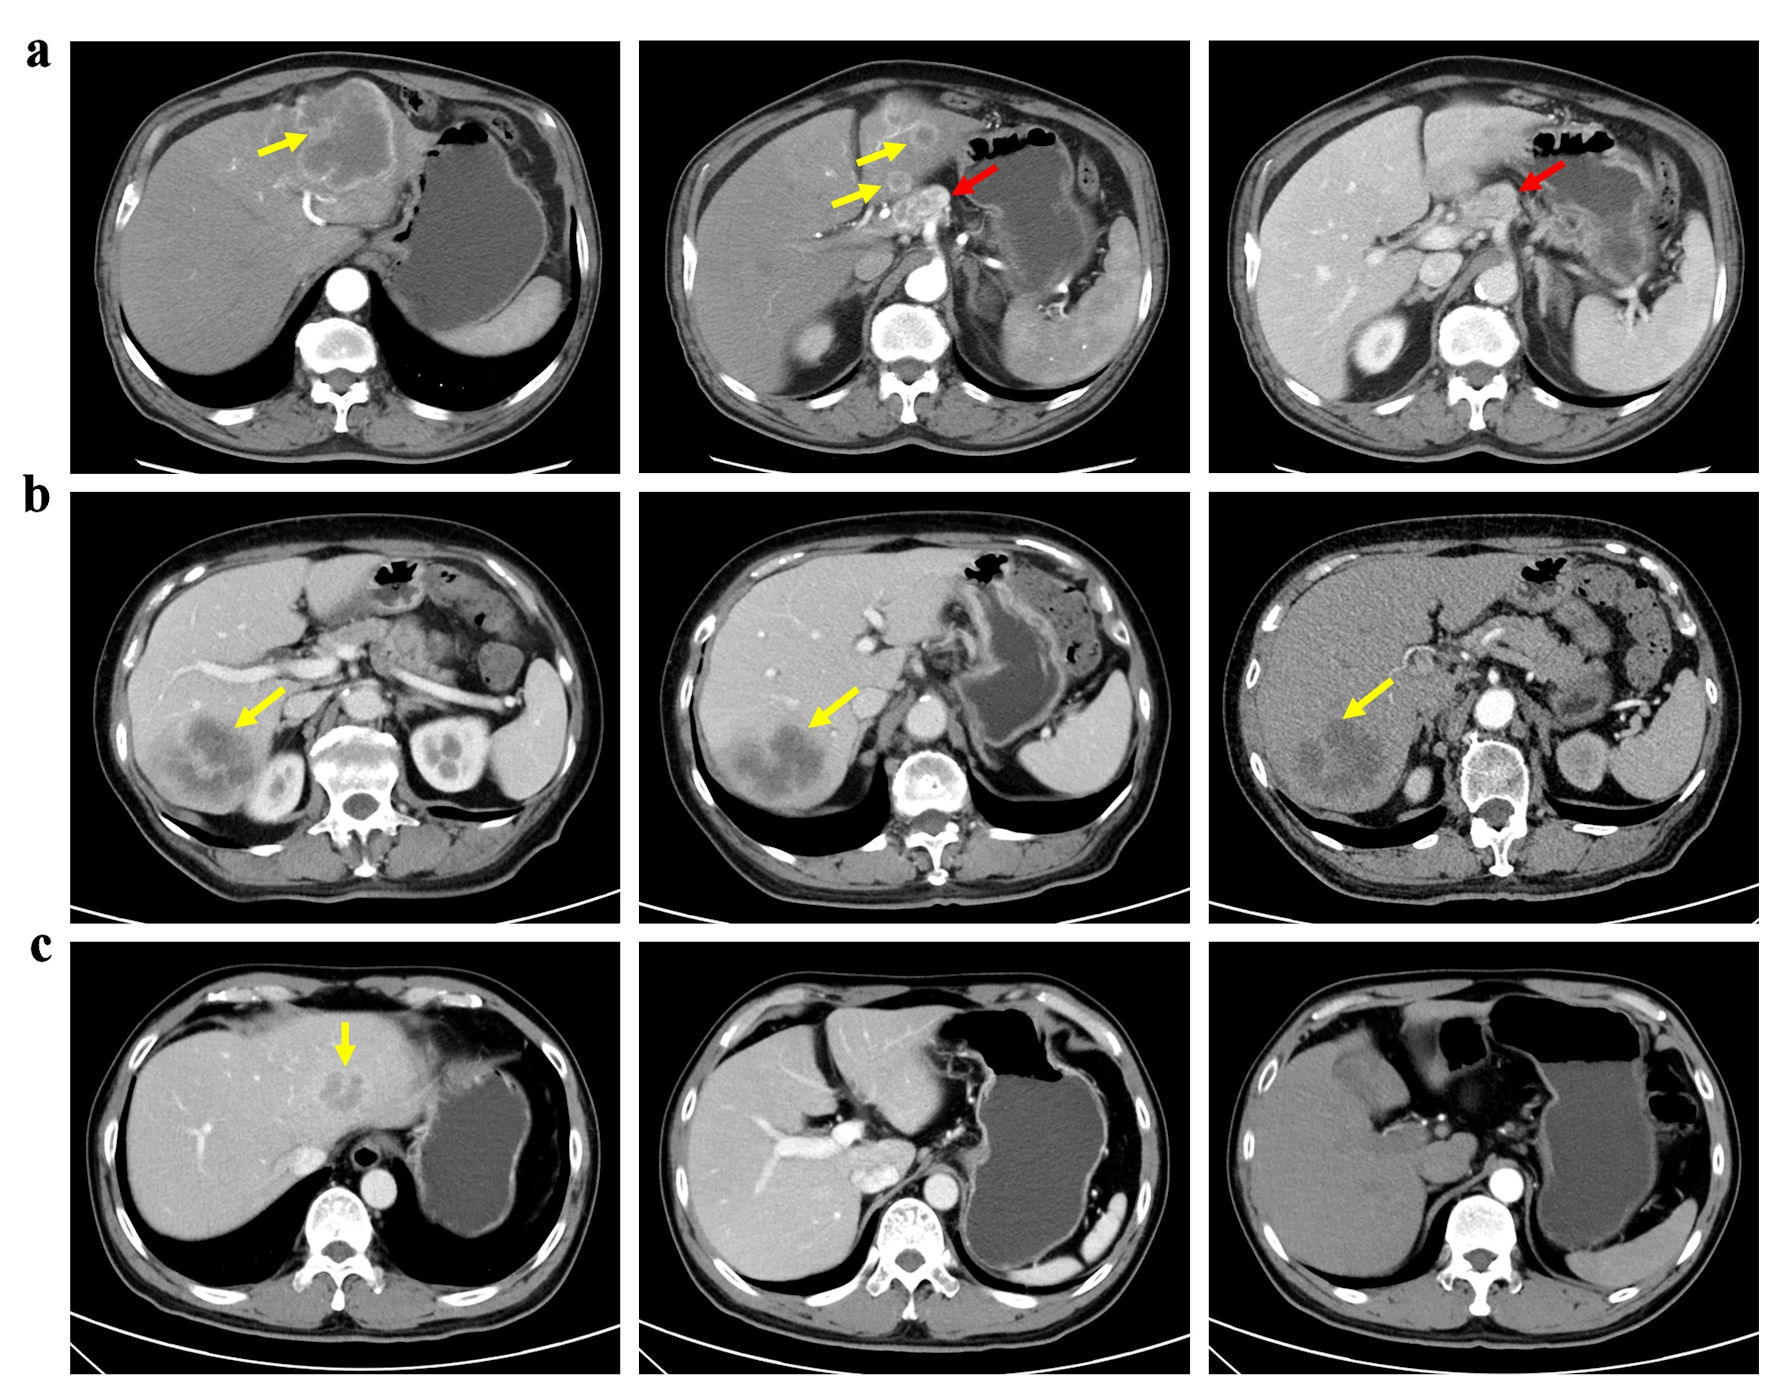

Clinically node-negative ICC was defined as patients with no suspicious or positive LNM evaluated by preoperative radiology findings [16]. Presence of lymph nodes > 1 cm, contrast enhancement at computed tomography (CT) or magnetic resonance imaging (MRI) and central necrosis or extra-nodal extension was proposed as clinically node-positive ICC [17, 18]. Patients without LND were defined as non-LND, while patients receiving LND were divided into LNM (+) and LNM (-) according to postoperative pathological status of lymph nodes (Fig. 2).

![]() Click for large image | Figure 2. Patients with different lymph node status of ICC. (a) A patient with clinically node-positive ICC received left hemi-hepatectomy and lymph node dissection. (b) A patient with clinically node-negative ICC underwent both liver resection and lymph node dissection based on suspicion of lymph node metastasis at multidisciplinary team discussion. Postoperative pathology confirmed no lymph node metastasis. (c) A patient with clinically node-negative ICC underwent liver resection only. Yellow arrows: tumor; red arrows: lymph node. |